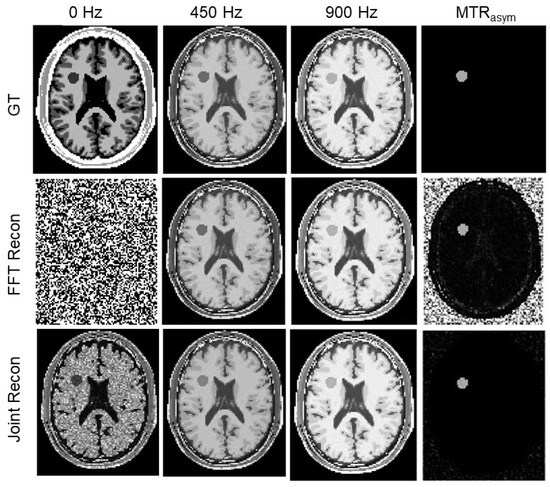

3.4. Results of Iopamidol Phantom Case